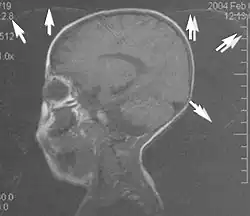

Metal artifacts occur at interfaces of tissues with different magnetic susceptibilities, which cause local magnetic fields to distort the external magnetic field. This distortion changes the precession frequency in the tissue leading to spatial mismapping of information. The degree of distortion depends on the type of metal (stainless steel having a greater distorting effect than titanium alloy), the type of interface (most striking effect at soft tissue-metal interfaces), pulse sequence and imaging parameters. Metal artifacts are caused by external ferromagnetics such as cobalt containing make-up, internal ferromagnetics such as surgical clips, spinal hardware and other orthopaedic devices, and in some cases, metallic objects swallowed by people with pica.[3] Manifestation of these artifacts is variable, including total signal loss, peripheral high signal and image distortion (Figs 3 and 4).[1] Reduction of these artifacts can be attempted by orientating the long axis of an implant or device parallel to the long axis of the external magnetic field, possible with mobile extremity imaging and an open magnet. Further methods used are choosing the appropriate frequency encoding direction, since metal artifacts are most pronounced in this direction, using smaller voxel sizes, fast imaging sequences, increased readout bandwidth and avoiding gradient-echo imaging when metal is present. A technique called MARS (metal artifact reduction sequence) applies an additional gradient, along the slice select gradient at the time the frequency encoding gradient is applied.